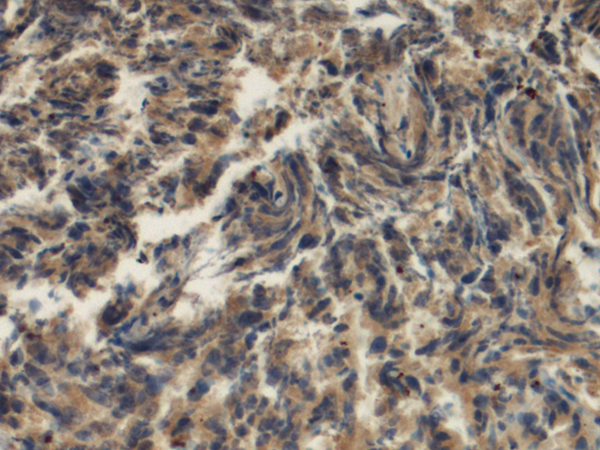

IHC positive control:

Human prostate cancer and Human ovarian cancer

IHC Recommend dilution:

100-300